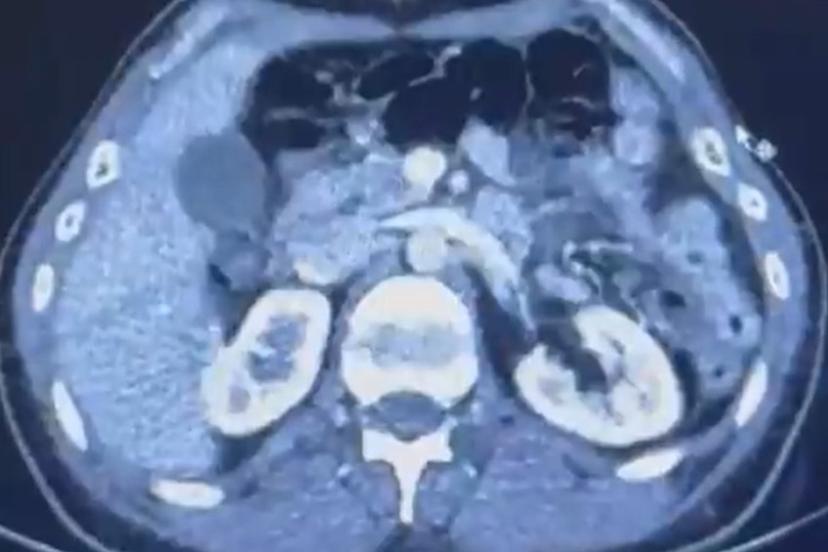

Edinilen bilgiye göre Narkotik Suçlarla Mücadele Şube Müdürlüğü ekiplerince uluslararası uyuşturucu madde ticareti yapan kurye şahıslara yönelik gerçekleştirilen çalışmalarda, İran’dan Türkiye’ye uyuşturucu madde getirdiği tespit edilen şüpheli şahısların yakalanması amacıyla operasyon düzenlendi. Düzenlenen operasyonda; S.C., R.B.C. ve G.M. yakalandı. S.C. ve R.B.C.’nin Kayseri Şehir Hastanesi’nde yapılan iç beden muayenelerinde, mide kısımlarında bulunduğu tespit edilen 50 adet kapsül şeklinde toplam 554 gram uyuşturucu madde ele geçirildi. Şüpheliler gözaltına alınarak haklarında ’Uyuşturucu Madde Ticareti Yapmak’ işlem başlatıldı.